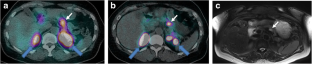

Fig. 2